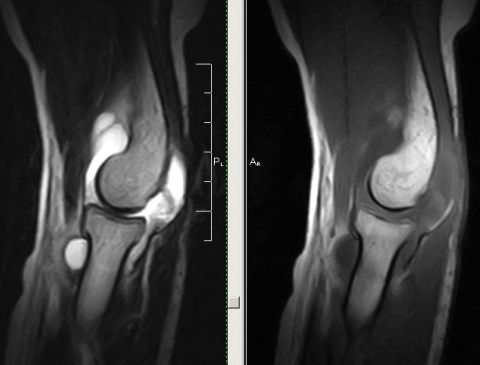

Вывих коленного сустава на МРТ

Вывих коленного сустава — болезненная травма, сопровождающаяся повреждением капсульно-связочного аппарата. Он может быть свежим (впервые полученным) или привычным (периодически повторяющимся, часто с полным разрывом передней крестообразной связки).

МРТ коленного сустава выполняется в трех взаимно перпендикулярных плоскостях, что позволяет выявить изменения, такие как повреждения внутрисуставного хряща, капсульно-связочного аппарата, менисков, ушиб костного мозга и околосуставных мягких тканей.